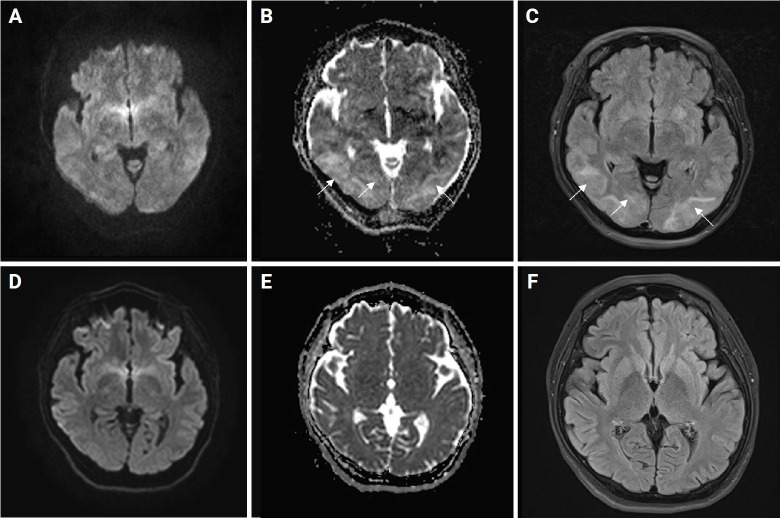

Hashimoto's encephalopathy (HE) is a rare disease of the central nervous system characterized by diverse neurological symptoms associated with elevated levels of antithyroid antibodies. Posterior reversible encephalopathy syndrome (PRES) is a clinico-radiological syndrome characterized by typical manifestations such as severe headache, altered mental status, visual impairment, seizures, and vasogenic edema. We experienced a patient with HE presenting with PRES who showed remarkable improvement subsequent to treatment with anti-seizure medication and corticosteroids. This case report underscores potential pathomechanisms and clinical significance.